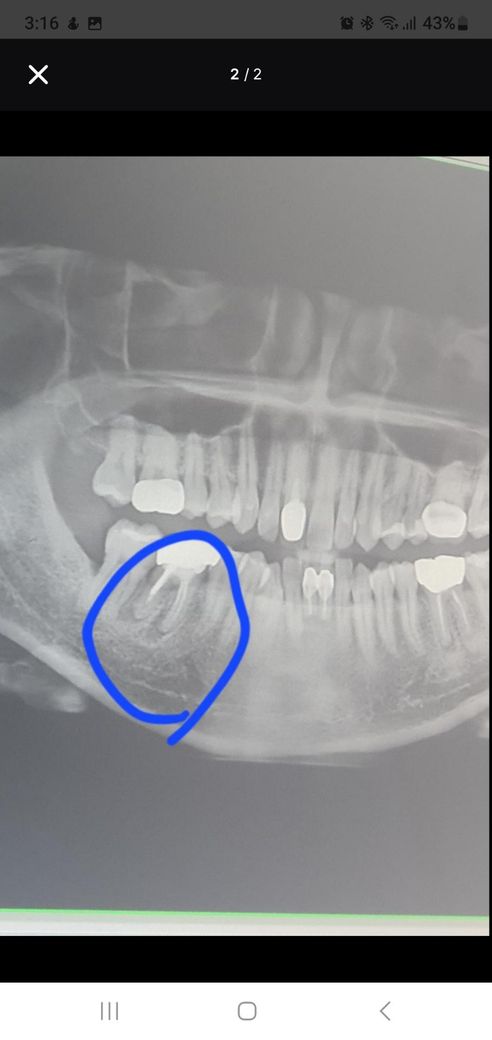

예전 25살쯤 금니 했던건데 최근 2~3달 쯤전 잇몸이 살짝 붓고 아픈듯 하드니 갑자기 염증이 튀어나왔어요

그전에 25년 11월말쯤 치과에서 스켈링 하면서 검사했을땐

염증은 있지만 지금 이상태를 일부로 치료 하진않는다고 넘기더라고요

이건 어떻게 바로 치료가 되는지 다시신경치료를 하는지 치근단수술을 하는지 발치를 해야하는지 알려주세요

재신경치료 내지는 치근단 절제술의 옵션이 있긴 하지만 엑스레이 상태보면 성공확률이 높지 않아 보입니다. 이미 뿌리끝으로 만연하게 염증이 잡혀있는 양상입니다.